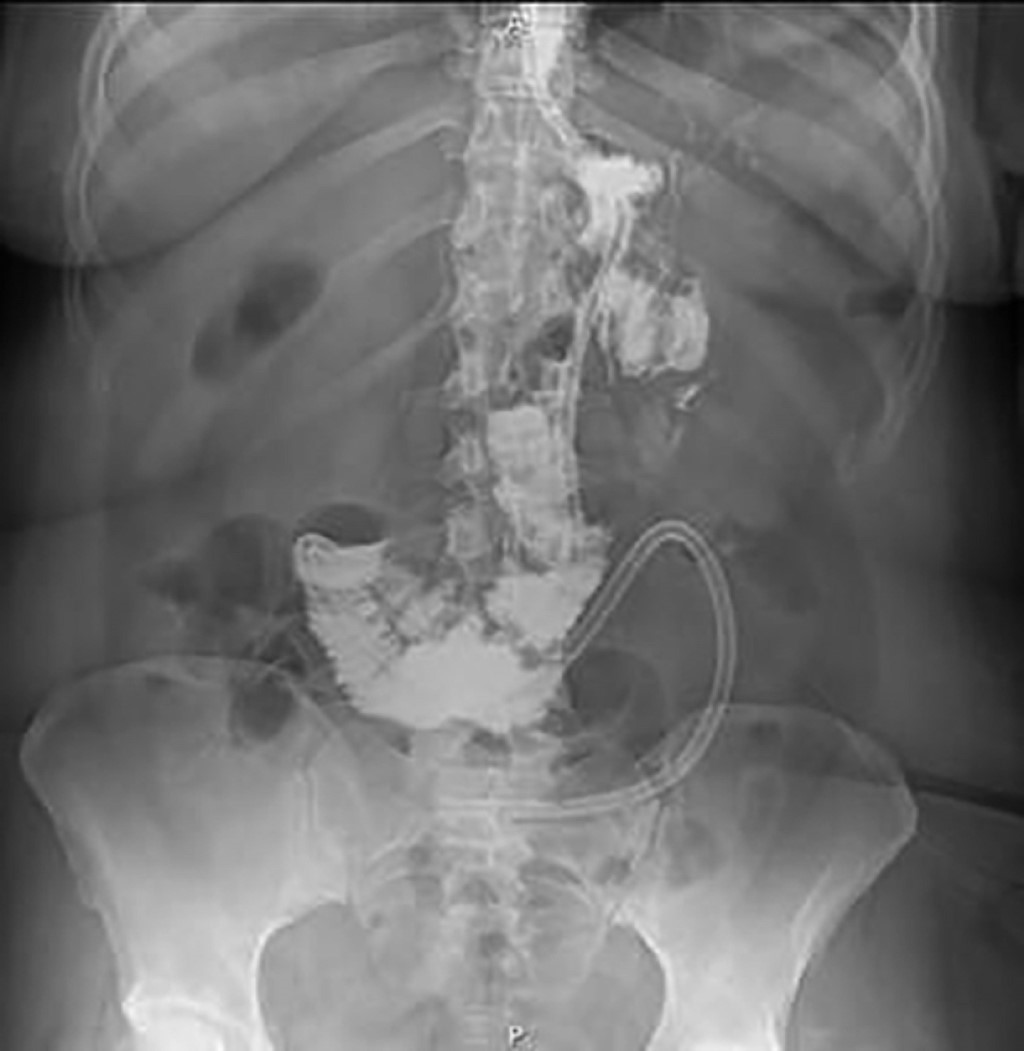

Introduction: anastomotic leak is a serious complication in bariatric surgery, and in BAGUA bypass it could be underreported, due to its low incidence, which highlights the importance of documenting the case. Clinical case: 38-year-old woman with a history of hypothyroidism, previous cesarean section and cholecystectomy surgeries, diagnosed with grade III obesity (BMI 41.9), underwent gastric bypass of an anastomosis (BAGUA) in a private setting. Thirteen days later she presented abdominal pain, fever and tachycardia; a CT scan revealed an 8 × 8 × 8 cm hematoma. The following day, she underwent laparoscopy which showed partial dehiscence of the gastrojejunoanastomosis, which was treated with evacuation of the hematoma and primary closure. Seven days later, she came to our unit due to persistence of abdominal symptoms, which led to a new laparoscopy with the presence of anastomosis leakage, evacuation of the hematoma and conversion to Roux-en-Y, placement of nasojejunal tube, leaving the hospital seventeen days later. Conclusion: the initial repair was not successful, but conversion to Roux-en-Y bypass and nasojejunal tube feeding proved to be safe and definitive solutions. It is crucial to develop surgical revision protocols for these complex cases.

Figure 1

Figure 2

Figure 3

Figure 4